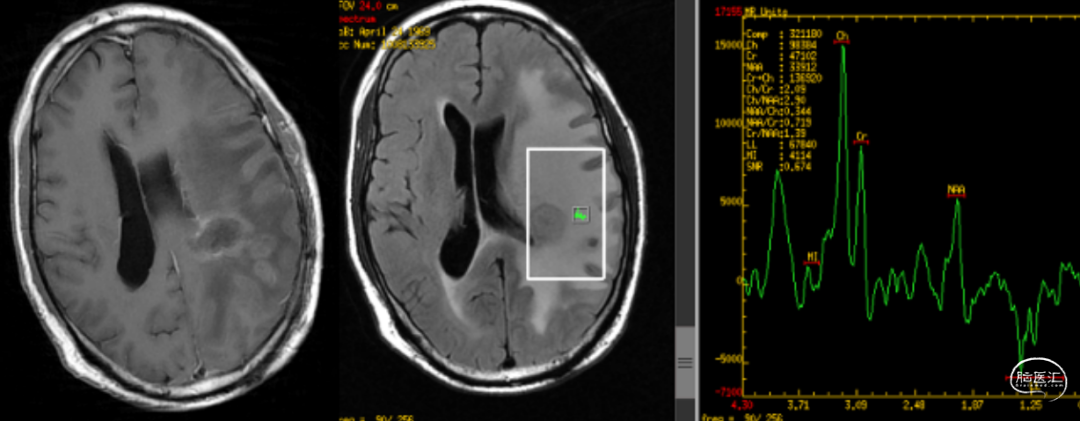

病理检测及分子基因检测结果

患者属IDH野生,TERT突变型GBM,预后约11.3个月

患者属MGMT无甲基化组(即甲基化均值<10%),其mPFS为7.2个月,mOS为13.4个月

MGMT启动子非甲基化,对替莫唑胺敏感度较低

TMB=1.35muts/Mb;微卫星稳定型(MSS)

影像学资料

男性患者,51岁,肿瘤切除后接受放化疗以及TTFields 术后病理检测及分子基因检测显示为胶质母细胞瘤(IDH野生,TERT突变),预后约11.3个月;MGMT无甲基化组( 即甲基化均值<10% ),mPFS为7.2个月,mOS为13.4个月 患者术后约1月开始进行同步放化疗,同步放化疗期间接受TTFields;期间出现额叶转移、对侧新发肿瘤、额叶新生肿瘤以及右侧脑室旁新生肿瘤等4次肿瘤进展,1次癫痫;根据患者具体情况动态调整放靶向药物以及免疫疗法药物,调整TTFields佩戴时间 远端进展的出现可能有:1.TTFields根据肿瘤位置进行个体化定位,TTFields强度集中于肿瘤发生位置,以达到最佳治疗效果;2.在出现远处肿瘤复发脑区,放射野未覆盖或覆盖剂量不足;3.使用TTFields的患者生存时间延长,所以更有机会观察到远端转移的发生 提高患者的依从性是TTFields改善胶质母细胞瘤生存的独立预后因素;TTFields期间,因皮疹/癫痫暂停TTFields4次,后经药物处理后病情好转并逐渐稳定

这是一例左顶叶原发性胶质母细胞瘤的患者,各项分子指标提示预后很差:1.IDH野生型;2.TERT启动子突变;3.MGMT非甲基化。从患者后续的治疗也可以看到治疗过程曲折,疗效反复,多次复发并出现颅内多灶播散。在整个治疗过程中,临床医生根据最新的循证医学证据,积极尝试了靶向、免疫等联合治疗方案,最终达到21个月的OS,优于历史数据的中位值。